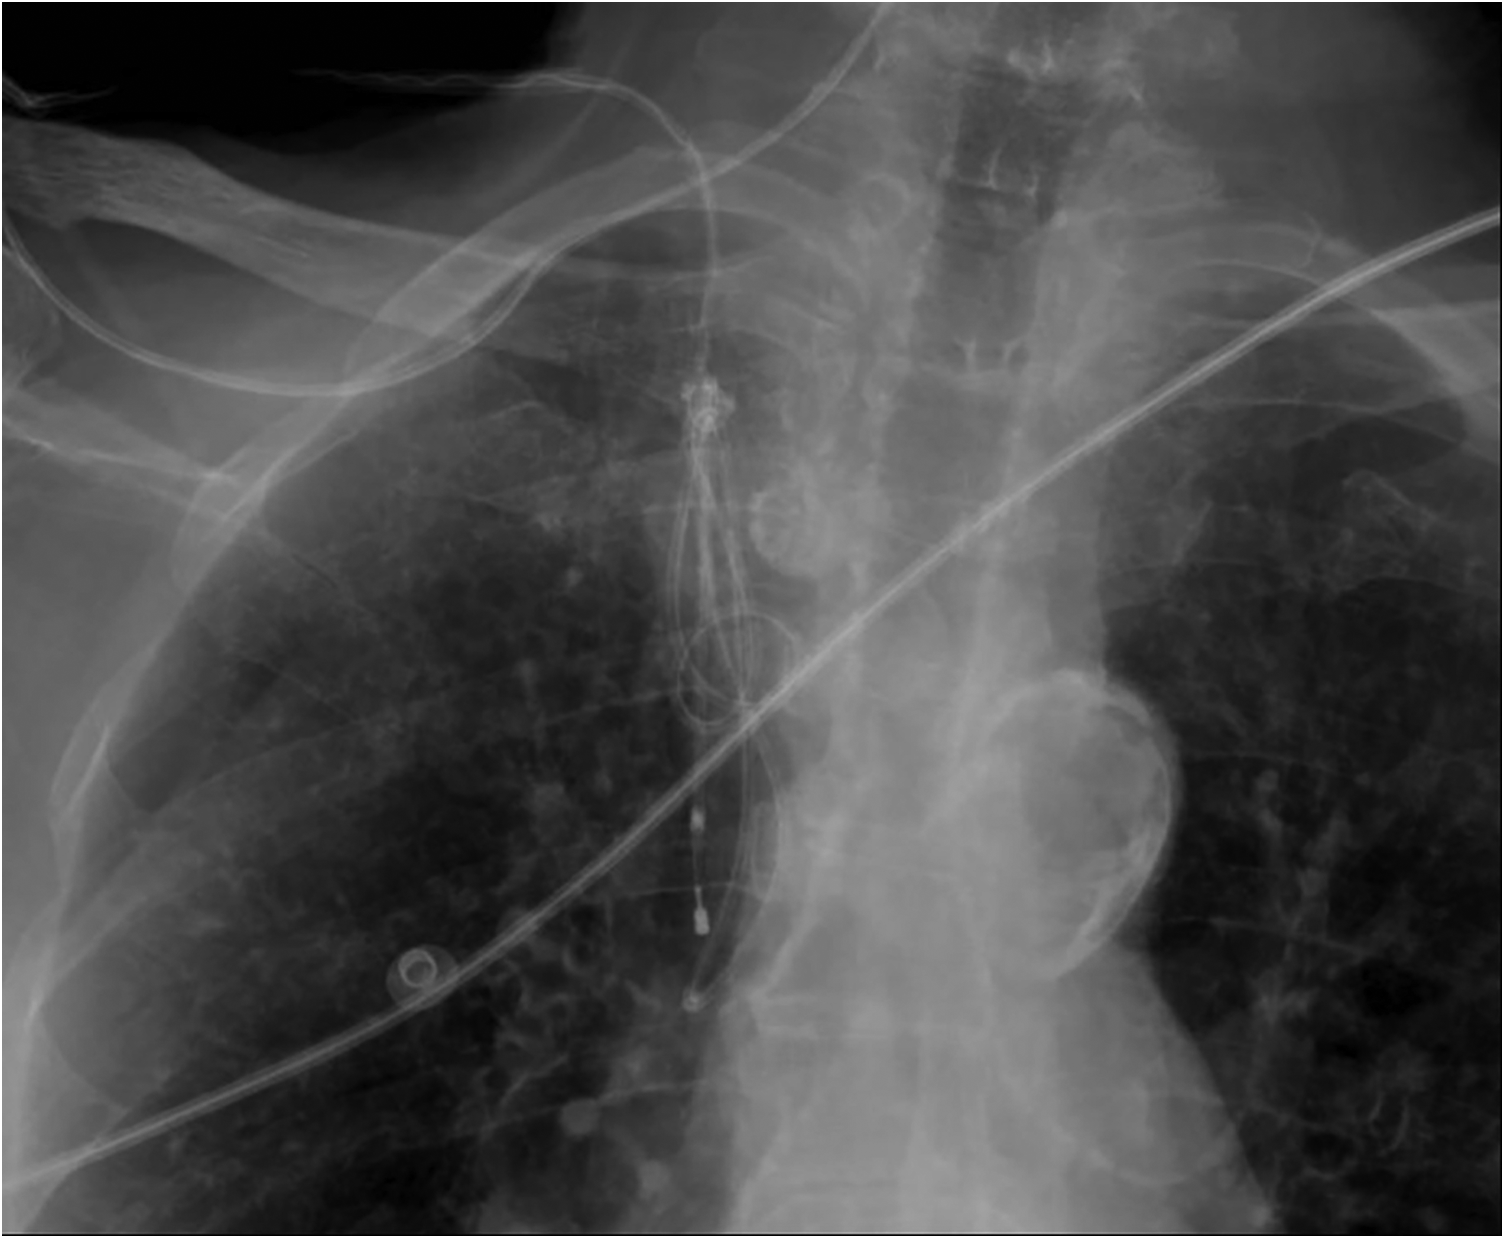

Figure 2

Chest x-ray detail showing the pacing lead loops within the brachiocephalic trunk and superior vena cava, with the knot trapped distal to the introducer and the catheter tip located in the superior vena cava.

A 7-Fr, 11-cm venous introducer was placed in the right internal jugular vein. In the absence of bedside fluoroscopy, the procedure was performed under ultrasound guidance with a second operator, and a 5-Fr, 110-cm balloon-tipped temporary pacing catheter (Spike Flow Bipolar Pacing Catheter, FIAB) was advanced. Despite correct connection to the generator and maximal output (20 mA) in VOO mode, there was no atrial capture (as expected in permanent atrial fibrillation) and no consistent ventricular capture, apart from sporadic beats when the catheter approached the tricuspid annulus. Ultrasound guidance was limited by a poor subcostal window and a suboptimal apical view in the supine position. After multiple maneuvers - withdrawal with the balloon deflated and readvancement with the balloon inflated - the catheter was advanced up to 55 cm without achieving capture. During subsequent withdrawal, the catheter became stuck at approximately 45 cm. A chest radiograph revealed a double loop of the pacing catheter with entrapment of a knot near the venous introducer (Figure 2). Meanwhile, the ventricular rate improved to 50–55 bpm on high-dose isoproterenol, so further invasive maneuvers were deferred overnight.